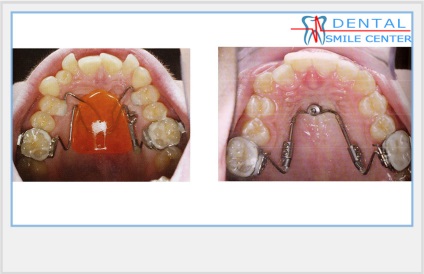

A szájüregi distaliziruschie apprat. Sok eszközök distalization zápfog. Készülékek ritkábban használtak, például a korlátozott hely a nyelvet. Nyelv nem tudja ellátni teljes funkcióját.

A fenti eszközök vannak kitéve szegmentális aktiválási, 1 alkalommal havonta. Azaz, 1 alkalommal havonta aktiváljuk az egyik oldalon, a második alkalommal - a második oldalon.

Felnőtt betegeknél az distalization zápfog a leggyakrabban használt mikro. A kapcsolási elrendezés microimplants distalization őrlőfogak részletes a „microimplants”.